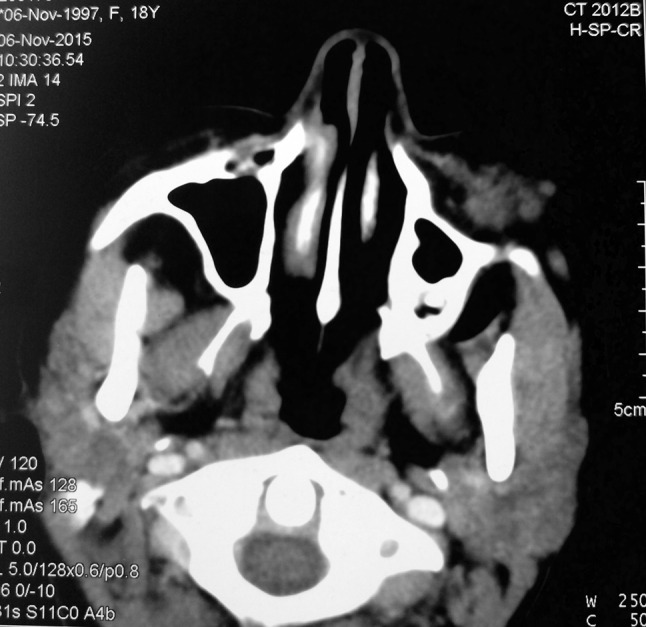

Contrast enhanced CT scan revealed an ill-defined, heterogeneously enhancing multilobulated lesion seen in subcutaneous plane of left cheek. There was no evidence of any bony erosion or intraoral extension as seen in Fig. 2 and Fig. 3.

Fig. 3.

Axial section of contrast enhanced CT scan showing ill-defined lesion in subcutaneous plane without bony erosion